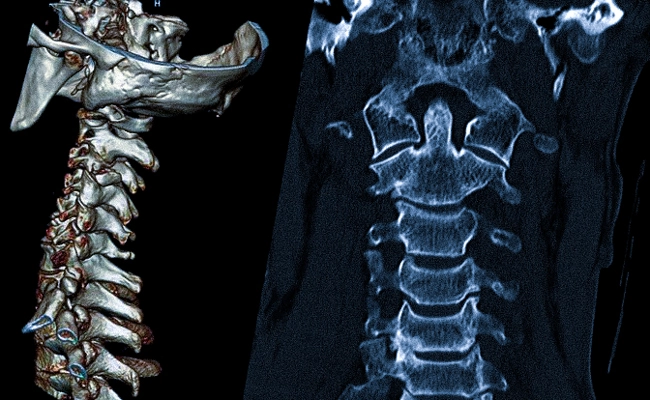

Компьютерная томография стеноза позвоночного канала

На данном изображении показан участок сужения спинального канала.

КТ проводятся с использованием рентгеновских лучей. Разные ткани тела по-разному реагируют на ионизирующее излучение. Более плотные структуры демонстрируют высокую рентгеновскую контрастность, что приводит к получению ярко выраженного сигнала. На изображениях, полученных в ходе исследования, кости и хрящи выглядят очень светлыми.

Этот метод диагностики применяется для более точной оценки состояния тел и отростков позвонков, межпозвоночных дисков, а также спинномозгового канала. Сужение последнего может приводить к сжатию мозговых структур и нарушению функционирования центральной нервной системы. КТ позволяет обнаруживать патологические изменения на ранних стадиях, что помогает выбирать наиболее эффективные методы лечения.

Стеноз позвоночного канала может быть вызван рядом факторов, включая остеохондроз, травмы, опухоли или врожденные аномалии. Поэтому КТ особенно ценна в диагностике, позволяя врачам получать трехмерные изображения, что значительно улучшает точность выявления патологий.